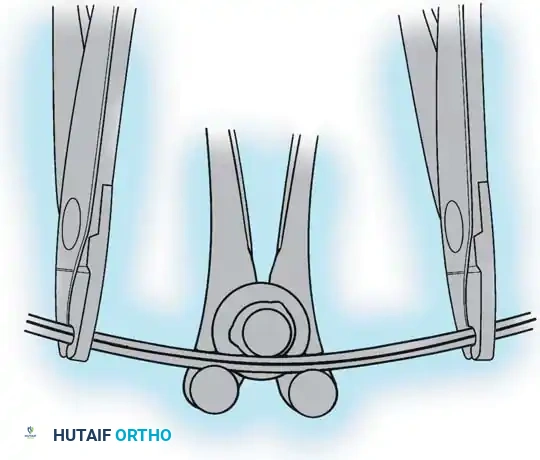

The Moe Technique (Lumbar Spine)

In the lumbar spine, the facet joints are oriented in a more sagittal plane, necessitating a modified approach.

Fig. 38-27: The Moe technique adapted for lumbar facet fusion, addressing the sagittal orientation of the joints.

- Utilize a small osteotome or a needle-nose rongeur to resect the adjoining joint surfaces.

- This creates a distinct rectangular defect within the sagittally oriented joint space.

- Pack this defect forcefully with cancellous bone graft.

- Proceed to decorticate the entire exposed posterior elements (laminae and transverse processes) using Cobb gouges, always directing force away from the spinal canal.